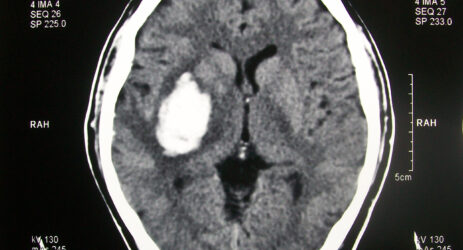

Tutti i danni della leggerezza dei medici sul web

Un miliardo di tac e radiografie sono finite online senza particolari protezioni. Il report di Greenbone Networks pubblicato da Techcrunch